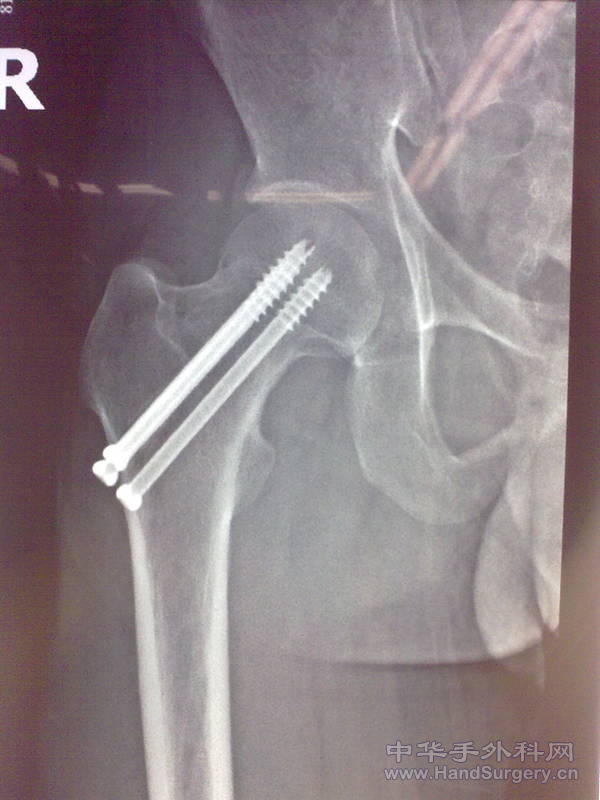

[其他] 股骨颈骨折三根钉治疗一例

第二张是术后1年的照片

术前片子位置还可以,术前垫高患臀术中适当牵引外展并内旋就可以了。在c臂下做这个手术我认为没有什么可炫耀的。

患者78岁 男性